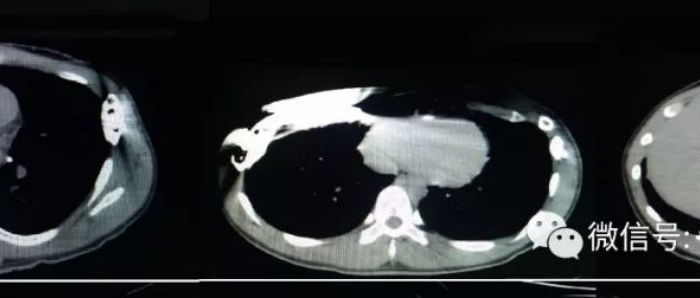

前胸壁有明显的凹陷畸形,凹陷呈横行沟状,累及两侧胸壁。胸壁正中及左侧胸壁各有一条手术疤痕,右侧胸壁则有两条手术疤痕。此外,胸壁左侧有一4x4cm大小的包块,其表面皮肤颜色加深,按压有明显的波动感。且包块向深部延伸,达到肋间。同时伴有轻度脊柱侧弯。最终患者被明确诊断为沟状胸。

2. 钢板放置的位置及方式不当:由术前影像检查结果可看出,钢板被置于沟状凹陷的上沿,且采用倾斜的方式放置。正确的做法应是将钢板置于凹陷的底部,这样才能有效地支撑并矫正凹陷的胸廓骨性结构。